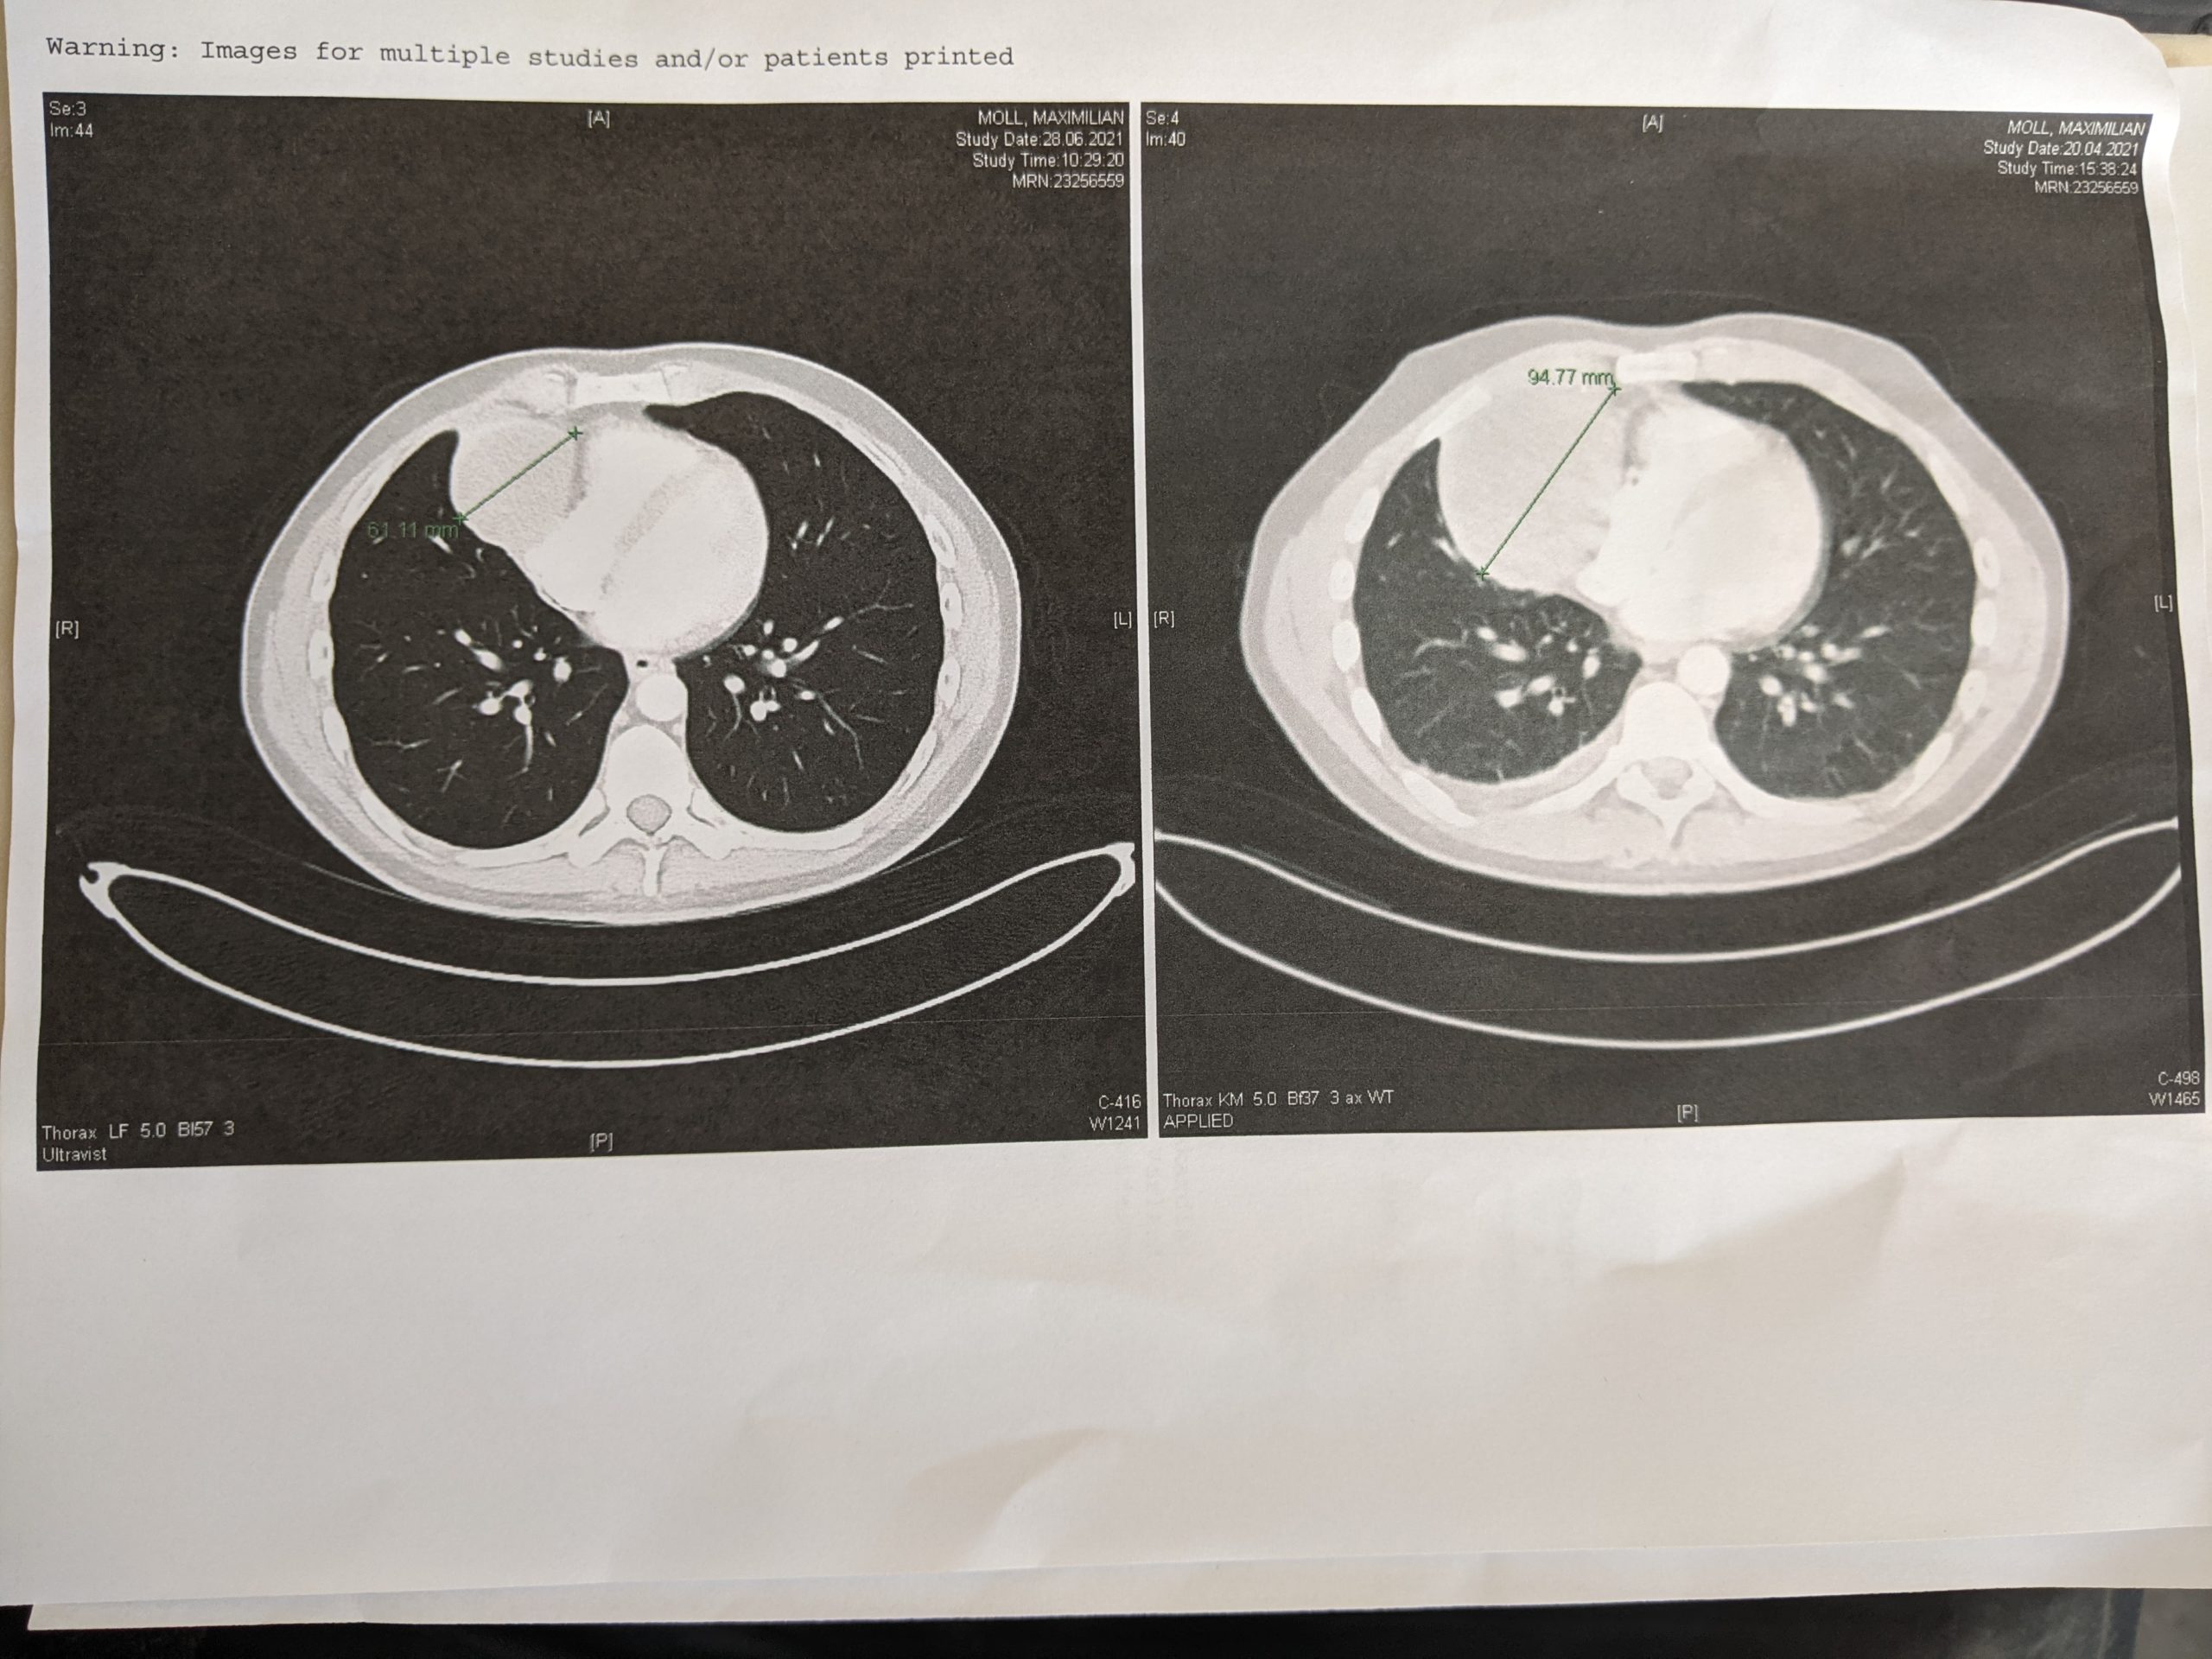

Vor diesem CT hatte ich nicht unbedingt Angst, aber es gab schon Zweifel, ob denn alles, was bisher gemacht wurde, etwas gebracht hat. Und ja… es hat es etwas gebracht. Je nach Messung hat Pumba 1/3 seiner Größe verloren und ist damit statt 9,477cm nun 6,1cm (s. dazu auch das Bild) groß. Hinzu kommt, dass ich keine Metastasen im Brustkorb oder im Bauchraum habe. Es gibt also Hoffnung.